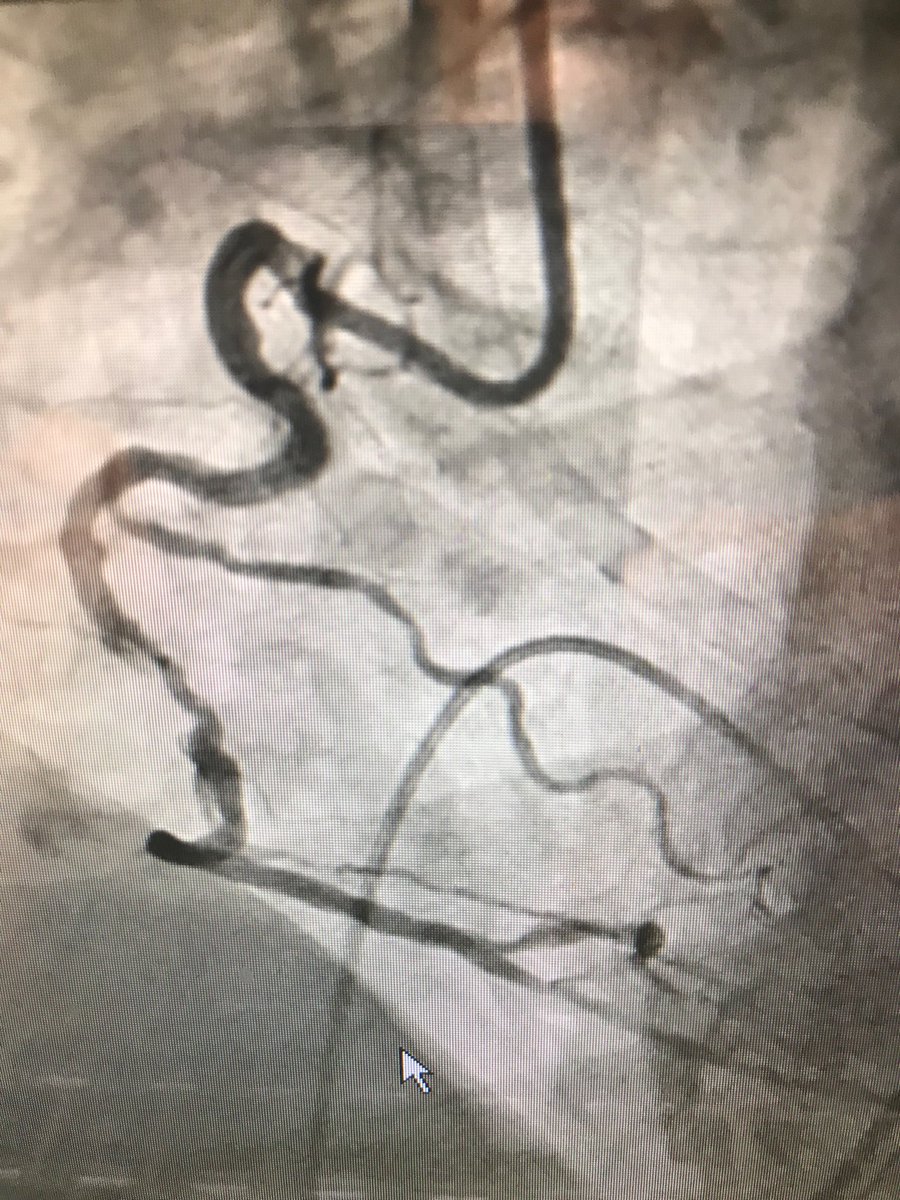

#protectedpci #RadialFirst #impella #safefemoral#ivus##unprotectedleftmainpci 61f#nstemi.6f45pinnacle inside 14f sheath .Successful #LMpci .left cfa occluded. bailout 014”grand slam/8x2balloon via rt radial. failed preclose ,safe balloon hemostasis while act240sec.#NoHematoma